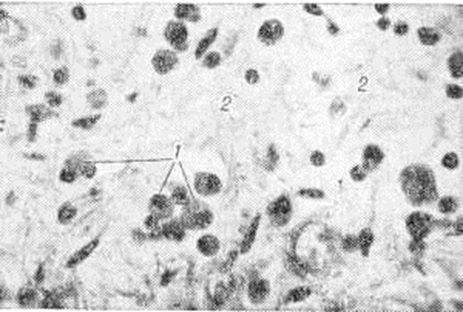

Рис. 1.

Микропрепараты миокарда животного при экспериментальном миокардите: а — очаговый кардиомиоцитолиз; стрелками указаны кардиомиоциты, подвергшиеся лизису; окраска железным гематоксилином по Гейденгайну, × 125; б — лимфогиетиоцитарный инфильтрат в интерстиции и отёк (указан стрелками); окраска гематоксилин-эозином, × 312.

При экспериментальном Миокардит установлены нарушения окислительно-восстановительных и энергетических процессов в миокарде. Метаболические нарушения сопровождаются очаговыми и диффузными морфологический реакциями, которые дают возможность выделить паренхиматозный, воспалительно-инфильтративный, некротический, гигантоклеточный и смешанный варианты экспериментального Миокардит Наряду с очаговым кардиомиоцитолизом (рисунок 1, а), отёком и лимфогистиоцитарными инфильтратами в интерстиции (рисунок 1, б) наблюдается выраженная реакция антиген—антитело и с помощью меток выявляются В-лимфоциты и фиксированные антитела. Подострый и хронический варианты экспериментального Миокардит морфологически характеризуются мозаичностью и сочетанием воспалительных изменений с атрофией, гипертрофией и склерозом в миокарде. В эксперименте показана обратимость острого и подострого вариантов Миокардит, особенно под влиянием экспериментальной фармакотерапии. На моделях экспериментального Миокардит апробирован ряд средств, оказавшихся эффективными для лечения Миокардит у людей: противовирусные препараты (интерферон, кутизон, ремантадин), антибиотики, вакцины и сыворотки (противодифтерийная, противоменингококковая, противогриппозная), иммуно депрессоры (имуран), ненаркотические анальгетики (бруфен, индометацин), гипосенсибилизирующие и противовоспалительные препараты, анаболические средства.